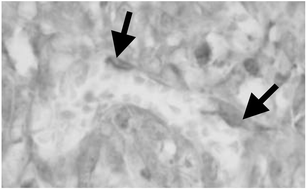

Neutrophils have become recognised as important contributors to the effectiveness of tumour eradication by photodynamic therapy (PDT). In this study, we have used the mouse SCCVII squamous cell carcinoma model to investigate the activity of neutrophils in tumours treated by PDT. Tumour levels of neutrophilic myeloperoxidase (MPO) demonstrated not only a massive and sustained sequestration of these cells in PDT-treated tumours but also revealed their activated state evidenced by the presence of released MPO. Among the adhesion molecules expressed on tumour vascular endothelium, ICAM-1 appears to be of primary importance in the invasion of neutrophils into PDT-treated tumours, because its functional blocking with monoclonal antibodies reduced the tumour cure rate. A marked upregulation of its ligands CD11b/CD18 and CD11c/CD18 found on neutrophils associated with PDT-treated tumours supports this assumption. To evaluate the role of inflammatory cytokines regulating neutrophil activity, neutralising antibodies were given to mice before PDT treatment. The results suggest that IL-1β activity is critical for the therapeutic outcome, since its neutralisation diminished the cure rates of PDT-treated tumours. No significant effect was observed with anti-IL-6 and anti-TNF-α treatment. Further flow cytometry-based examination of neutrophils found in PDT-treated tumours revealed that these cells express MHC class II molecules, which suggests their engagement as antigen-presenting cells and involvement in the development of antitumour immune response.